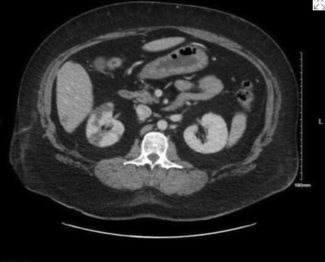

Dieter Brummund, MD; Angela Chang, MD; Vanitha Vasudevan, MD; Tony Shao, MD; Christopher Salgado, MD

A complex case of aortic graft salvage highlights flap selection challenges in a radiated, contaminated abdomen following sarcoma resection.